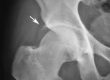

SVF treatment Knee Osteoarthritis India. SVF stands for ” Stromal vascular fraction”. It is a biological treatment for knee osteoarthritis.

This lady underwent #SVF treatment of #knee #osteoarthritis India. Listen to her testimonial. She has got complete pain relief from the procedure. Visit www.orthobiologicsurgeryindia.com for more testimonials and information. If you want this procedure for your loved parents, email me drvenlat@kneeindia.com